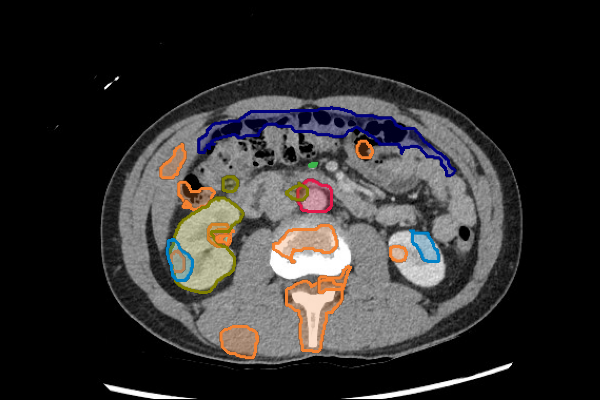

Legend

Slice 1

Slice 2

Slice 3

Slice 4

Slice 5

Slice 6

Slice 7

Slice 8

Slice 9

Slice 10

Slice 11

Slice 12